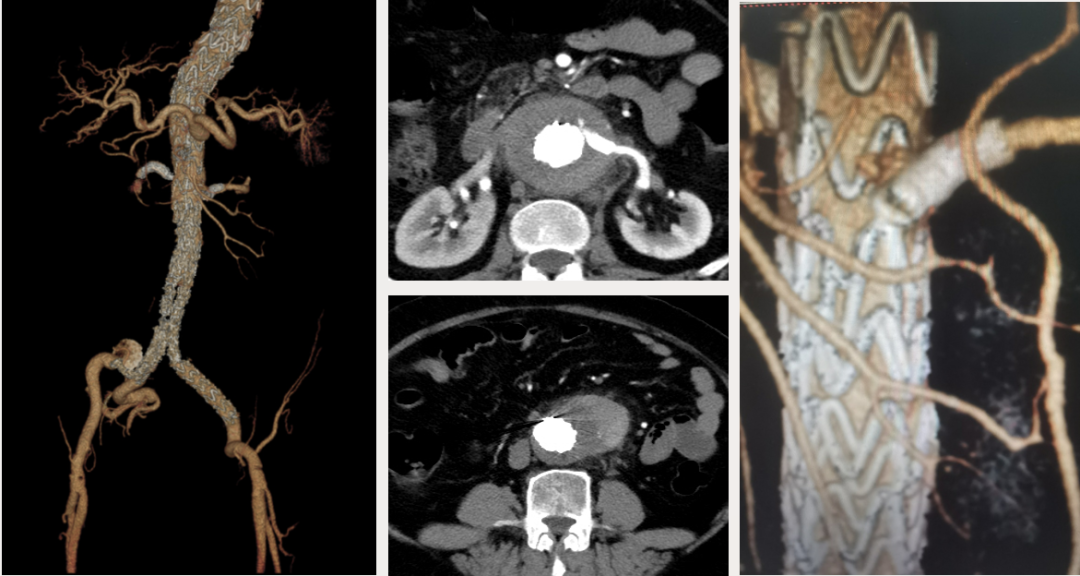

病例:复杂TAAD多次手术后,IIIc型内漏

术后2年随访:动脉瘤增大、左肾支架脱出

★ 大动脉瘤或偏心性动脉瘤术后

如果突然体位变化,有可能主体支架移位导致分支支架从窗口或内脏血管附着处脱出,引起内脏动脉急性阻塞和缺血。

预防措施:

建议至少置入两个分支支架,以固定主体和分支支架。